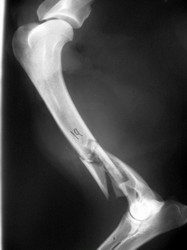

PRÁCTICAS CURSO DE FIJACIÓN EXTERNA PERFECCIONAMIENTO.

Húmero.